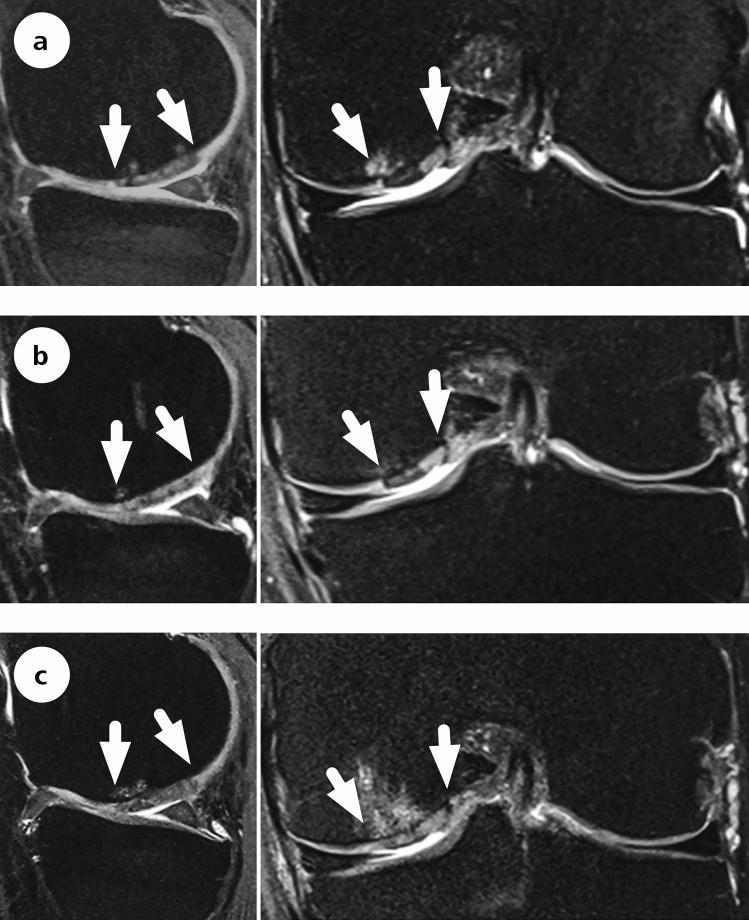

Forty-seven patients were randomized and treated either with MFx (n = 13), sutured AMIC (n = 17) or glued AMIC (n = 17) in a prospective, randomized, controlled multicentre trial. The Modified Cincinnati Knee Score, a visual analogue scale for pain and MOCART score were used to assess outcomes over 10 years post-operatively.

All treatment arms improved in the first 2 years, but a progressive and significant deterioration in scores was observed in the MFx group, while both AMIC groups remained stable. MOCART scores were comparable between groups.

方法

结果